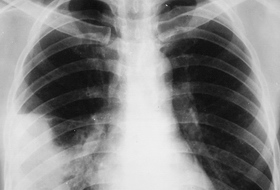

Vremea capricioasă a determinat o creştere uşoară a cazurilor de pneumonii

Din evidenţele Direcţiei Judeţene de Sănătate Publică, în prima săptămană a lunii s-au înregistrat peste cinci sute de cazuri de infecţii acute respiratorii, dintre care 30 de persoane au necesitat internare.

Purtătorul de cuvant al Direcţiei de Sănătate Publică Ialomiţa, Mihaela Dumitrescu, spune că deşi numărul de viroze a scăzut, incidenţa pneumoniilor a crescut uşor în acestă perioadă.